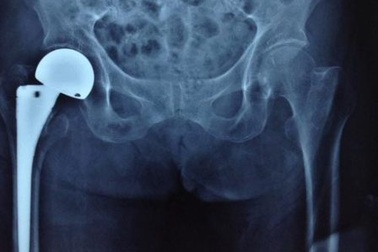

Bệnh viện quận thay khớp háng cho cụ bà gần 100 tuổiBị gãy liên mấu chuyển khớp háng bên phải khiến cụ Sang không thể ngồi dậy được. Tại bệnh viện quận 2, bác sĩ đã thực hiện thành công ca phẫu thuật “có một không hai” thay khớp háng lưỡng cực cho bệnh nhân gần 100 tuổi.